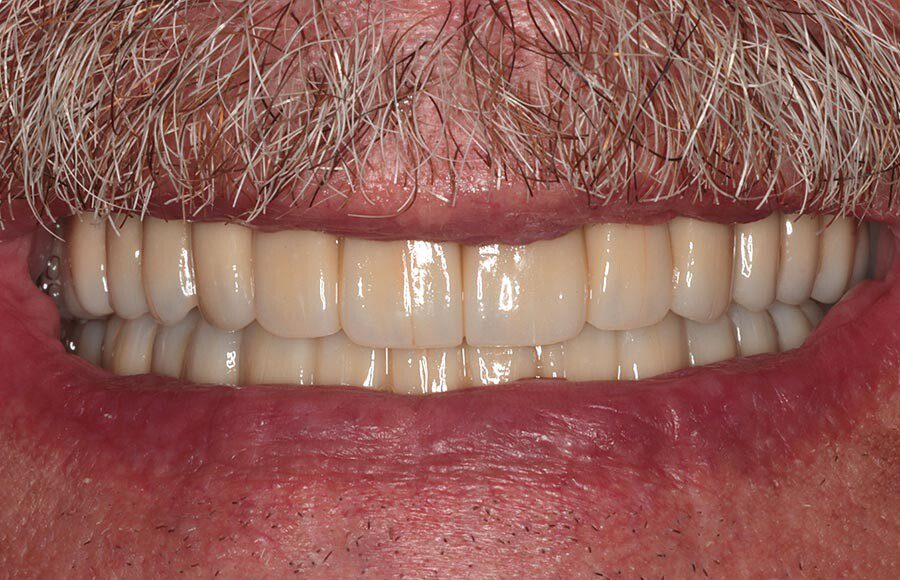

Smile GalleryImplant RestorationsFull Mouth Implant Restoration 1 of 13 Pre-operative smile Pre-operative smile Pre-operative frontal view, lips retracted Pre-operative panoramic image (note bone levels) Post-surgical panoramic image Surgical temporary bridge (note convex contours) Delivery of surgical temporary bridges in both upper and lower Two weeks post-op surgery and temporaries (note amazing tissue response) Three months post- surgery. (Note tissue development) Definitive implant bridges (FP-2) Post-treatment panoramic image Final result smile Final result smile